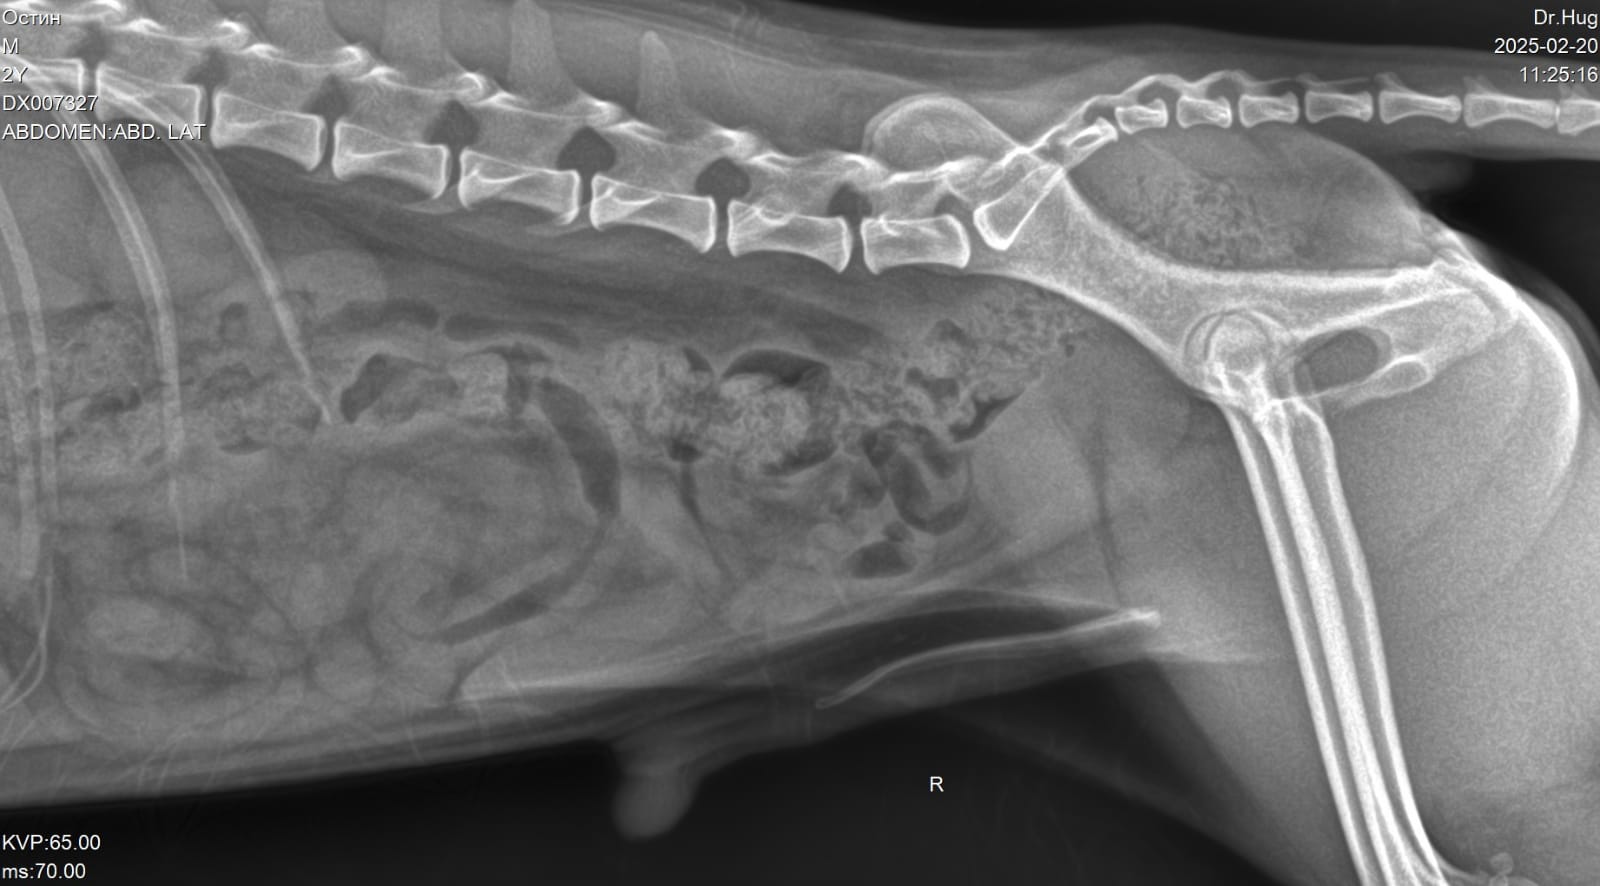

Светлана с Остином посетили врача.

Еще